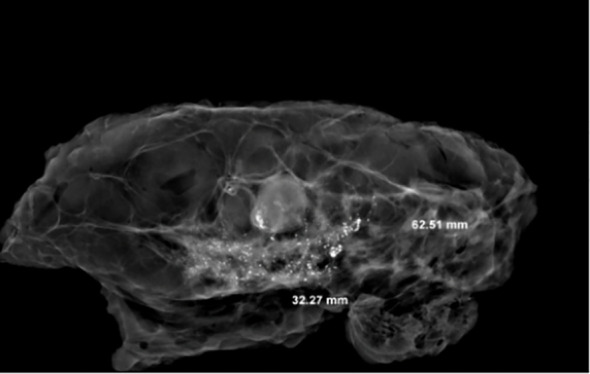

The treatment of breast cancer has gradually developed from the initial simple surgical treatment to the current comprehensive treatment plan with surgery as the center, supplemented by chemotherapy, radiotherapy, immunotherapy, endocrine therapy, etc. This is breast cancer research in imaging, surgery, The inevitable result of multidisciplinary comprehensive development such as pathology (1). NACT not only benefits more breast cancer patients, but also brings many problems and challenges to pathologists (2). Specimen selection and evaluation of important pathological parameters are critical to assessing the extent of treatment response, so it is important to recognize that histopathologists play a key role in this multidisciplinary environment. However, there is no uniform standard for the selection of tumor bed materials. This means that taking common methods for breast tumor beds after neoadjuvant may lose important parameters and cause great errors in the RCB score (3,4). According to the latest American Joint Committee on Cancer (AJCC) classification, taking macro- and micro-tissues to evaluate the size range (ypT) of residual cancer after neoadjuvant treatment of the tumor bed is the best combination. After neoadjuvant therapy, tumor bed changes can be roughly divided into two types: concentric contraction; non-concentric contraction (Figures 9,10). Concentric contractions are more common in HER2 overexpression and triple-negative or basal-like types, while non-concentric contractions are mostly luminal breast cancer. When the chemotherapy effect is good, the fibrosis and necrosis often occur in the tumor bed area, and it is often difficult to distinguish the existence of the parenchymal component of the tumor with eyes. Therefore, when the non-concentric contraction tumor bed approaches/reaches complete remission, it is difficult for pathologists to choose materials because they are easy to miss.

Figure 9.

The tumor showed a centripetal atrophy in CXS images. CXS, cabinet X-ray system.

Figure 10.

The tumor showed a non-centric atrophy in CXS image. CXS, cabinet X-ray system.